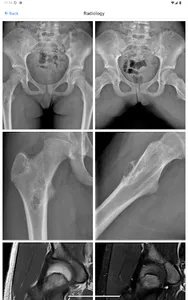

BoSTT brings the user a real experience of frequent and rare, typical and more unusual cases of bone and soft tissue tumours. Each case has a clinical history, high resolution radiology and pathology images, diagnosis, treatment and learning points.